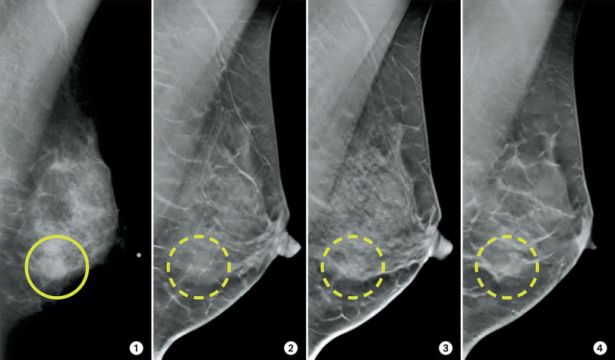

3D Mammography

Greater accuracy, fewer call-backs

We combine screening and diagnostic imaging in one platform, including 3D mammography for superior accuracy. This helps detect cancers earlier, even in dense breast tissue, when treatment is most effective.

Our Siemens Mammomat 3000 system delivers sharp, detailed images with reduced false positives. That means fewer call-backs, less anxiety, and faster clarity when you need it most.

Finds cancers earlier than traditional 2D mammograms

Reduces unnecessary anxiety and repeat scans